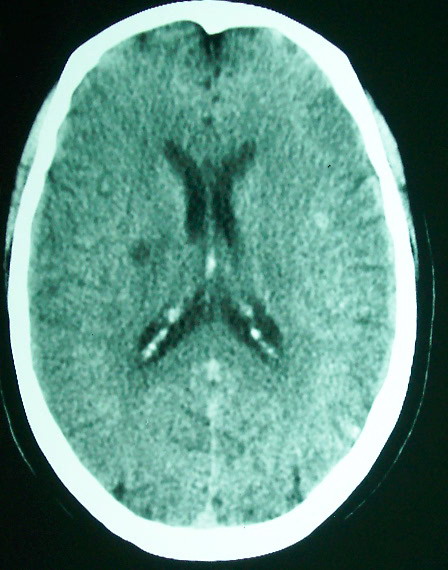

标题: CT18022:颅内多发稍高密度影

f     60    左侧肢体活动无力3天余,    神志情,  无抽搐史   无发热   否认囊虫接触史

有囊有节有钙化,这个表现符合混合型脑囊虫病.请结合临床资料并进行补体结合试验.

有囊有节有钙化,考虑混合型脑囊虫病.